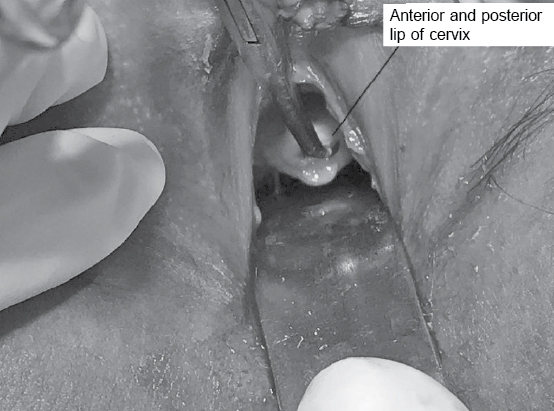

Per speculum examination showed a small-sized cervix with both anterior and posterior lips (Fig. 4).

Figure 4. Per speculum examination - Note small size cervix with both anterior and posterior lips.

Per vaginal examination – vagina admitted one finger and was 9 cm in length. Dimpling of external os was felt.